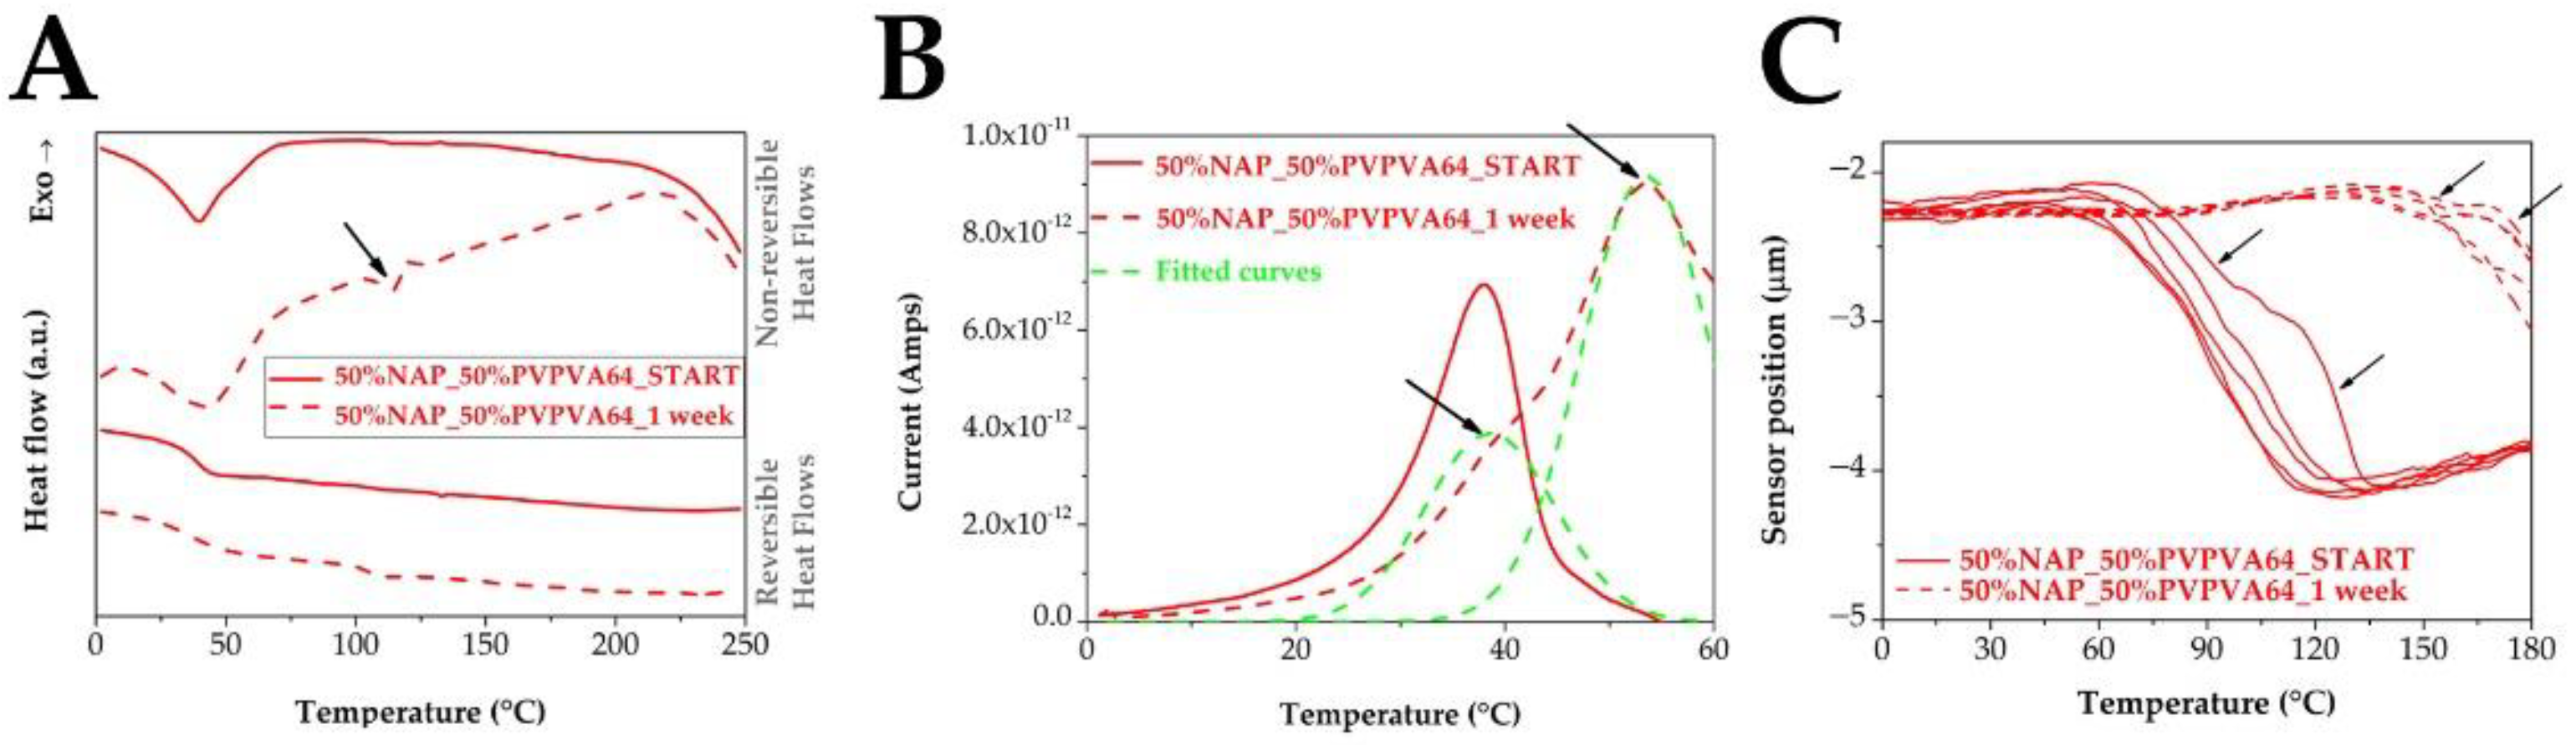

3.3. Effect of the Stress Stability Tests

3.4. Correlations between the Measured Tg Values and the Stability